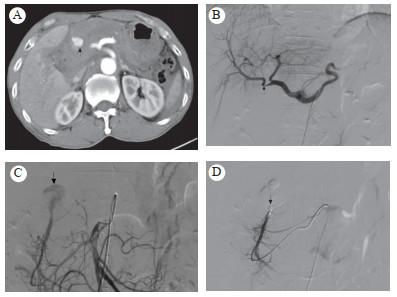

病例2患者男,38岁。因重物砸伤胸腰腹部疼痛1 h入院。无昏迷、呕吐、呕血,无胸闷、气急、呼吸困难,无腹胀、便血、血尿。查体:血压85/56 mmHg,心率120次/min,神志淡漠,上腹部见横行条片状青紫,胸廓挤压征阳性,呼吸音粗,腹肌紧张,呈板状腹,压痛反跳痛明显,肝脾肋下未及,肝区叩痛,肾区无叩痛,移动性浊音检查不合作,肠鸣音减弱。血常规:血红蛋白66 g/L,红细胞1.96×1012/L。CT检查示肝破裂,胰腺头颈部条状低密度,局部结构欠清,胃十二指肠动脉近段斑点状造影剂外溢(图 2A),右肾上腺挫伤伴血肿,多发肋骨骨折,盆腹腔大量积血。入院诊断:重物砸伤、闭合性腹部损伤、创伤性肝破裂、右肾上腺挫伤、失血性休克、多发肋骨骨折。给与输血补液扩容治疗同时急诊DSA:采用5F RH导管至腹腔动脉造影(碘海醇12 mL,速率4 mL/s,压力300 psi),造影示肝动脉走行正常,胃十二指肠动脉起始段局部隆起(图 2B),未见明显造影剂外溢,超选至胃十二指肠动脉造影, 其开口处见团块状造影剂外溢(图 2C),使用COOK 5 mm钢圈2个及1 mm明胶海绵颗粒适量栓塞后复查造影示造影剂外溢消失(图 2D),患者血压回升108/66 mmHg,心率下降至96次/min。术后保守治疗,未见复发出血,术后患者有低热、恶心、呕吐、腹痛、腹胀、胸痛、胸闷等表现,经对症处理后好转,未发生消化道出血胃肠道坏死或穿孔。

| A:胃十二指肠动脉近段斑点造影剂外溢;B:胃十二指肠动脉起始段局部隆起,未见造影剂外溢;C:超选后胃十二指肠动脉开口处见团块状造影剂外溢;D:钢圈栓塞后造影剂外溢消失 图 2 病例2的CT和造影检查结果 |